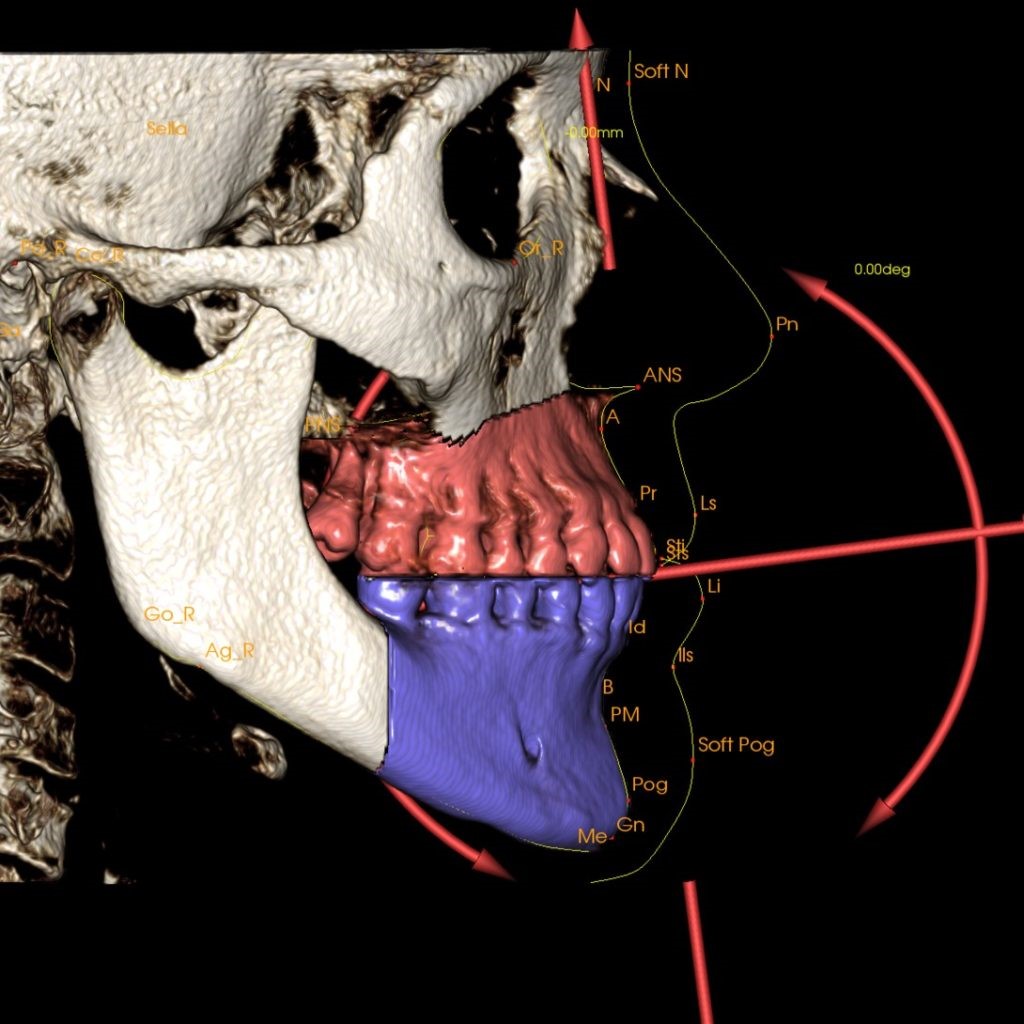

2. Ứng dụng trong chỉnh nha:

CBCT đã được sử dụng trong chỉnh nha nhờ vào khả năng về hình ảnh với FOV (quang trường) lớn, bao gồm tất cả những điểm mốc cho việc phân tích sọ nghiêng. Việc phân tích mối quan hệ xương hàm hình ảnh 3 chiều cần bao gồm nền sọ, xương mặt và mô mềm trên khuôn mặt

Với phim chụp CBCT, bác sĩ chỉnh nha có thể coi tình trạng răng ngầm, hướng mọc của các răng, tương quan và sự phát triển xương hàm, vị trí xương để đặt minivis, phân tích các thông số chỉnh nha về thẩm mỹ khuôn mặt, đánh giá kết quả trước và sau khi chỉnh nha của bệnh nhân.

Phân tích chỉnh nha trên phim CBCT